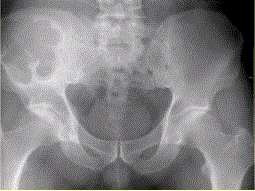

问题 患者男,28岁,右下腹及臀部疼痛5个月余。查体:右髂骨外后侧压痛,右下腹可触及一软组织包块,质韧,固定。行骨盆正位CR、骨盆CT及MR扫描见下图。 此病变最可能的诊断是

选项 A.骨囊肿 B.动脉瘤样骨囊肿 C.骨结核 D.骨巨细胞瘤 E.硬韧带样纤维瘤

答案 B